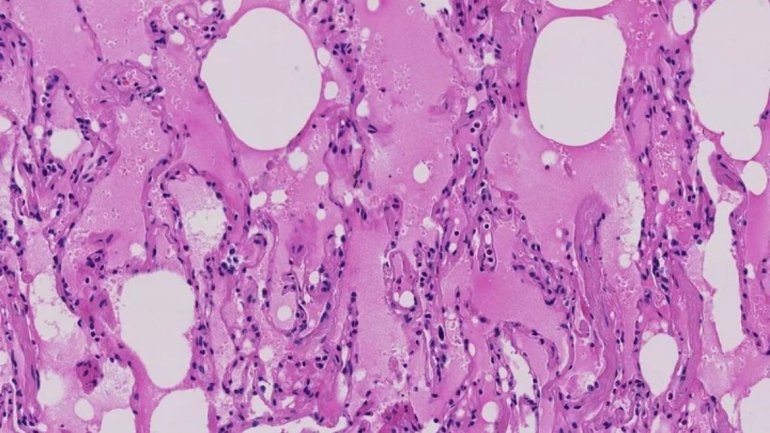

La inflamación y el flujo de oxígeno dificultado pueden hacer que esas zonas de los pulmones se llenen de fluidos, pus y células muertas. Puede producirse entonces una neumonía, una infección en los pulmones.

Algunas personas tienen tanta dificultad para respirar que necesitan que se les coloque un respirador. En los peores casos, conocidos como Síndrome de Dificultad Respiratoria Aguda, los pulmones se llenan de tanta cantidad de fluidos que ningún de apoyo respiratorio es suficiente y el paciente muere.

Shu-Yuan Xiao, profesor de patología de la Escuela de Medicina de la Universidad de Chicago, ha estudiado informes de patología de pacientes con coronavirus en China. Señaló que al parecer el virus comienza en las zonas periféricas de ambos lados del pulmón y puede tardar un tiempo en llegar al tracto respiratorio superior, la tráquea y otras vías respiratorias centrales.

Un estudio reciente de un equipo encabezado por investigadores de la Escuela Icahn de Medicina de Mount Sinai reveló que más de la mitad de 121 pacientes de China tenían tomografías computadas normales al comienzo de su enfermedad. Ese estudio y los trabajos del Dr. Xiao muestran que, a medida que la enfermedad avanza, las tomografías muestran “opacidades de vidrio esmerilado”, una especie de velo borroso en partes del pulmón que son evidentes en muchos tipos de infecciones respiratorias virales.

Esas zonas opacas pueden dispersarse y engrosarse en distintos lugares conforme la enfermedad se agrava, creando lo que los radiólogos llaman un patrón de “crazy paving” o empedrado desordenado en la tomografía.